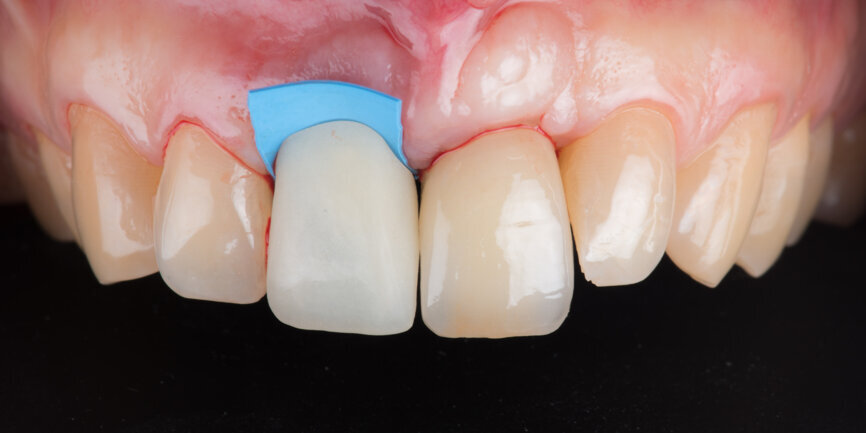

A Regular Base (RB) titanium temporary abutment for a crown was placed and a laboratory-made shell was positioned without interference with the temporary abutment (Fig. 9). The surgical site was protected with a small piece of rubber dam (Fig. 10), and the abutment was connected to the shell with a dual-curing luting composite (Fig. 11). The development of a proper emergence profile will be done extra-orally (Fig. 12) to produce the screw-retained temporary crown.

Before placing the provisional crown, the gap between the implant and the buccal plate was filled with a particulate xenograft material (cerabone, botiss biomaterials). The graft was packed up to the gingival margin according to the dual-zone principle described by Chu et al. (Fig. 13).[7] The screw-retained temporary crown was then torqued to 35 N cm (Fig. 14).